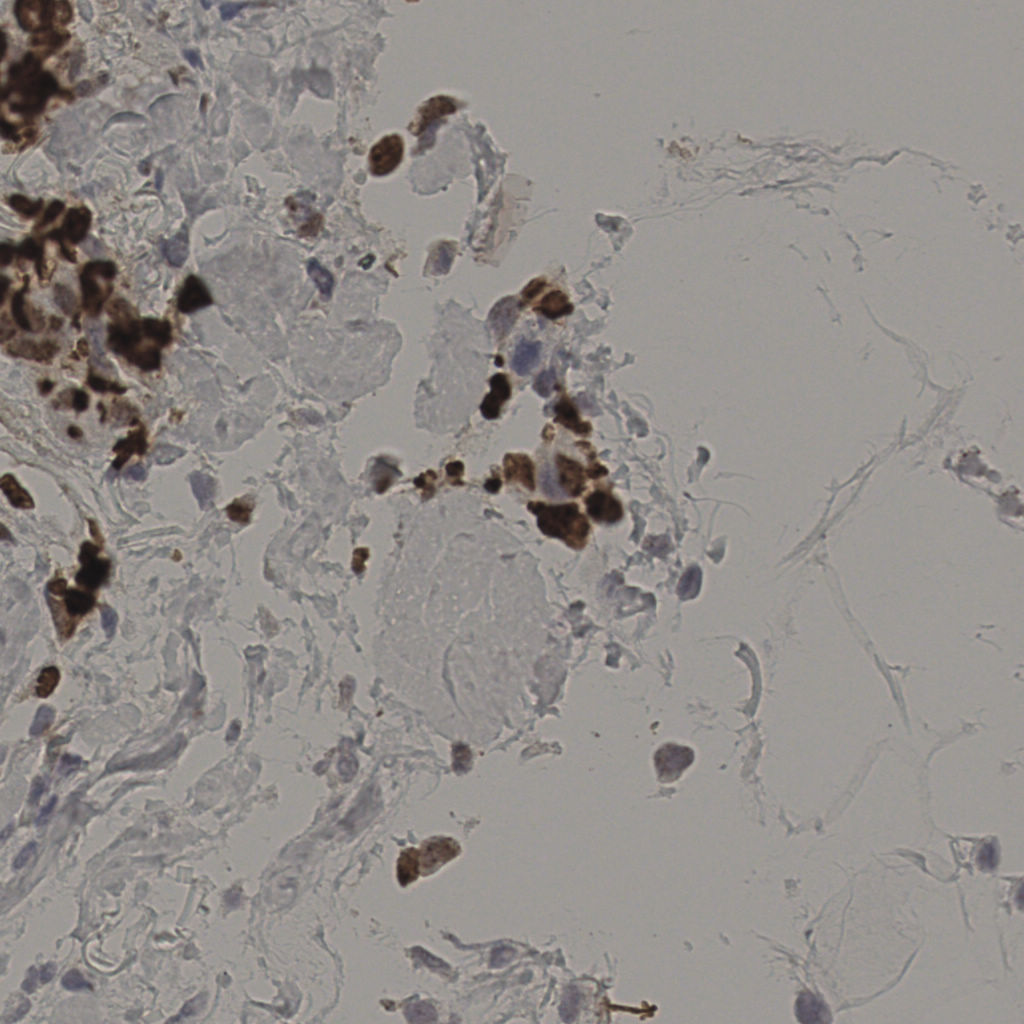

17.75%

Ki67 指数

阴 7986

阳 1723

切片统计

总切片

2640

有效

412

已标记

412

有效率

16%